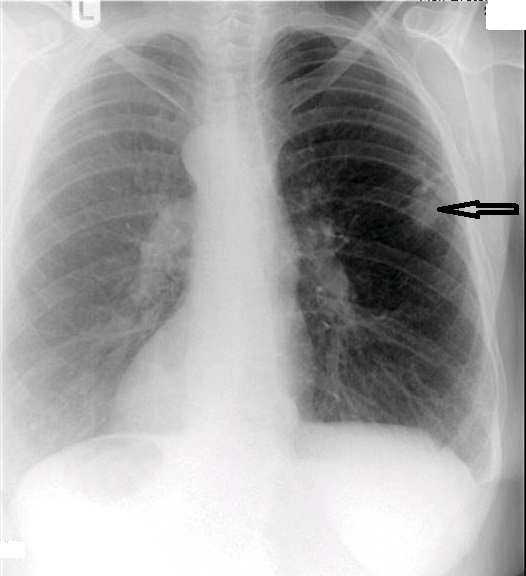

On figure 1, the original AP thoracic projection, an oval density is seen in the periphery of the right lung field (white arrow points to lesion). A thoracic and lumbar scoliosis is also seen. The lateral projection revealed multilevel degenerative change, as well as compression fractures at T9 and T10, with a focal kyphotic deformity seen in figure 2. Since a PA chest projection was not included, a chest series consisting of PA and lateral views was suggested to better evaluate the suspected lesion.